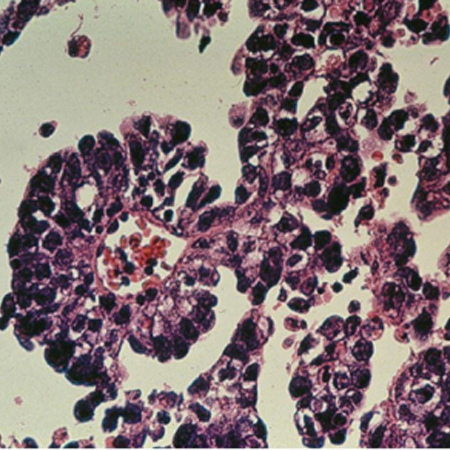

Ovarian cancer

Microscopic view of ovarian cancer

From the collection of Justin C. Chura, MD, Cancer Treatment Centers of America, Philadelphia, PA